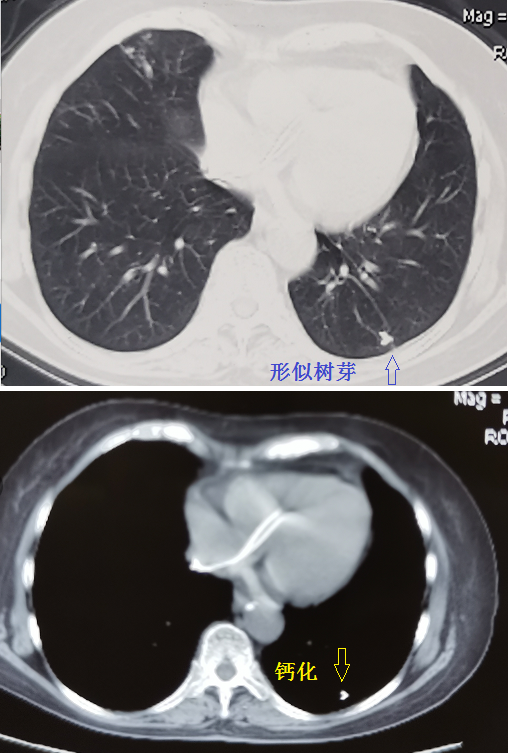

肺部ct基础读片认识树芽征